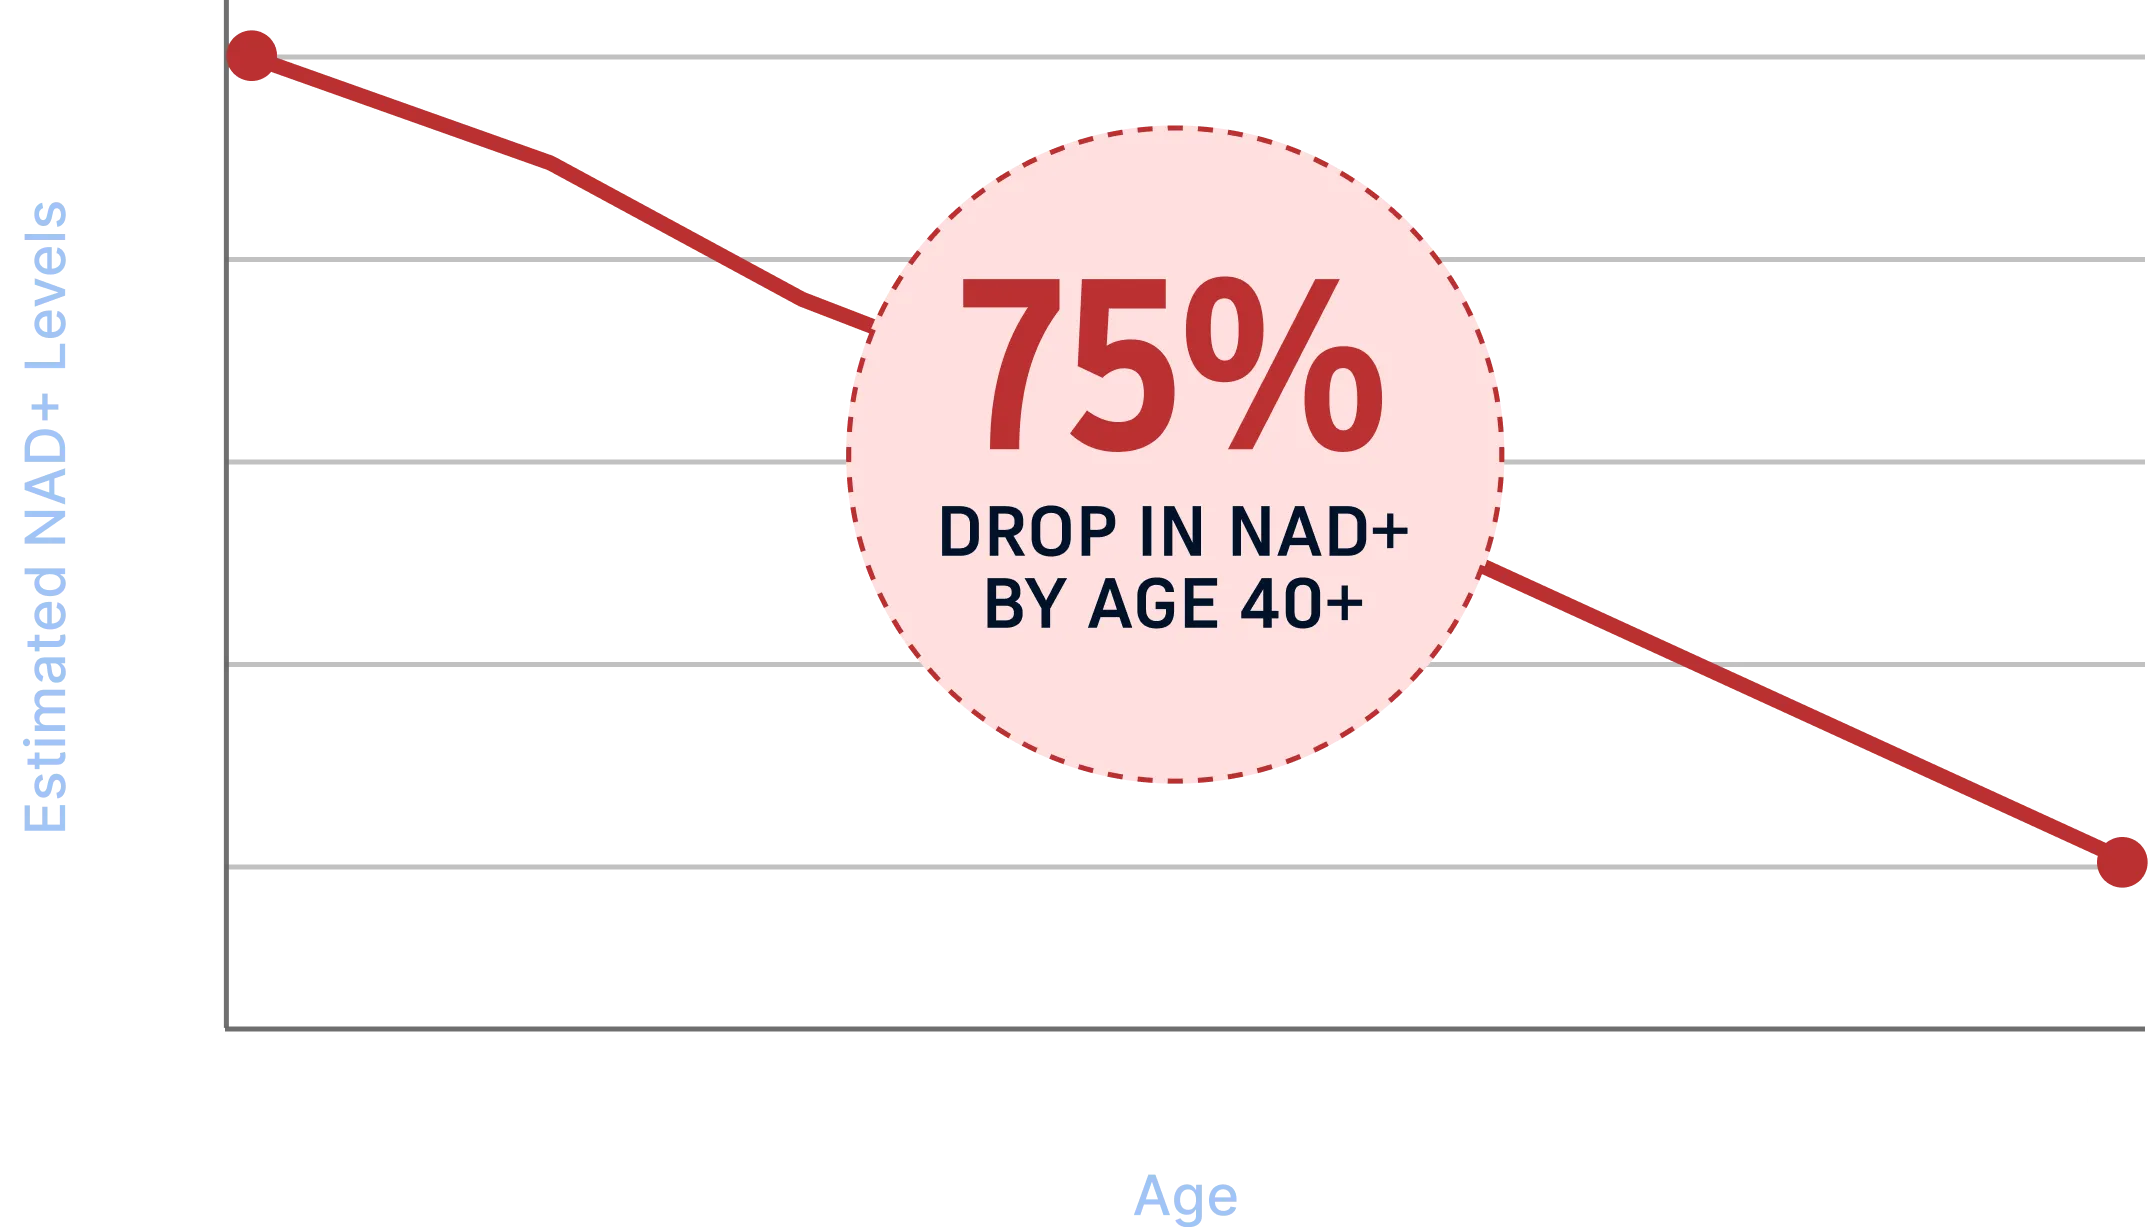

The Real Reason Men Lose Energy After 40

NAD+ naturally declines as men age, slowing

the

cellular processes that keep you energized, focused, and

resilient. Lower NAD+ leads to weaker circulation,

slower recovery, reduced mental clarity, and a drop in

daily performance.

Energy Decline

Reduced Focus

Slower Recovery

Weaker Circulation